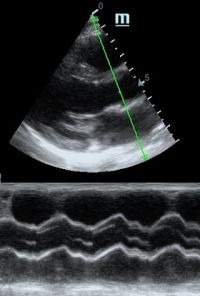

Оценка кооптации нижней полой вены ещё никогда не была такой простой и точной, никаких лишних деталей, просто устанавливаем клипер по анэхогенному участку.